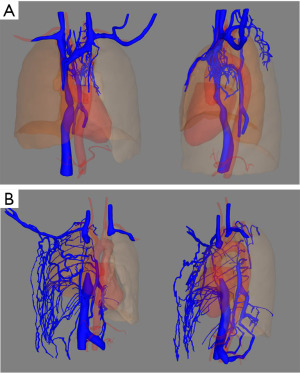

No tumor recurrence was found after a 44-month follow-up and abundant collateral circulations could be seen in postoperative imaging (Figure 3).

The patient already had collateral circulations before surgery and more abundant collateral circulations could be seen after SVC resection alone without venous reconstruction (Figure 6). After a 31-month follow-up, there was no recurrence of tumor (Figure 7).

We reported two cases of SVC resection alone without venous reconstruction for thymic tumors, one with the azygos vein reserved and the other with azygos vein resected. These patients recovered well without severe obstructive complications and did not require anticoagulation therapy. Long-term follow-up showed obvious collateral circulations and no tumor recurrence.

Collateral circulations may develop after chronic SVC obstruction (11). In case 1, preoperative imaging showed that the patients had an obvious collateral vein on the left side of the aortic arch originating from the left innominate vein but it was hard to know if the collateral circulations could completely compensate for the loss of the SVC-innominate vein route. So, we prepared for venous reconstruction before surgery and used intraoperative IJVP to decide whether to perform the reconstruction. We also found a thick collateral vein (left superior intercostal vein) consistent with the imaging intraoperatively (Figure 2B). IJVP was below 30 cmH2O when clamping the SVC, supposing adequate blood return to the heart. Therefore, SVC and bilateral innominate veins were resected without venous reconstruction, while azygos vein were reserved. In case 2, the tumor invaded inside the SVC and azygos vein was also invaded. When clamping the SVC and azygos vein, IJVP was also below 30 cmH2O and therefore SVC, bilateral innominate veins and azygos vein were resected without venous reconstruction. These patients recovered well postoperatively without severe obstructive complications. Long-term follow-up showed more abundant collateral circulations and no recurrence of tumor.